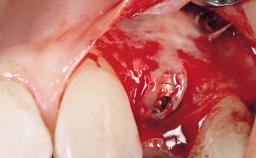

Immediate Flapless Placement of an Implant in a Maxillary Left Central Incisor Site

A 42-year-old female patient was referred to our clinic at the School of Dentistry of the University of São Paulo in November 2004, presenting a deficient restoration in the upper left central incisor. The clinical examination revealed no gingival retraction or any signs of gingival inflammation and, therefore, previous periodontal treatment was not considered. The patient presented a high lip line at full smile and a thin tissue biotype. This combination characterized a high-risk situation from an anatomic point of view, which required careful preoperative planning and cautious surgical execution.